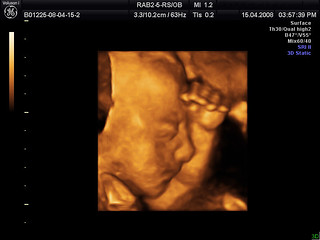

Baby Bob in 3D - We went for our 4D ultrasound yesterday and… - FlickrLos Ultrasonidos 4D son una tecnología avanzada que se utiliza para visualizar el desarrollo fetal durante el embarazo. Estos ultrasonidos proporcionan imágenes tridimensionales y en tiempo real de la estructura y movimiento del feto, lo que permite a los médicos tener una comprensión más clara del desarrollo y la salud del feto. Además, los Ultrasonidos 4D también ofrecen imágenes en tiempo real de los movimientos del feto y su expresión facial, lo que permite a los padres conectarse más con su bebé en desarrollo.

Pero, ¿cómo funcionan los Ultrasonidos 4D exactamente? Los Ultrasonidos 4D utilizan ondas sonoras de alta frecuencia para producir imágenes en tiempo real del feto en el útero. La sonda se coloca en la barriga de la madre y las ondas sonoras viajan a través de la piel y el tejido para llegar al feto. La sonda mide la cantidad de tiempo que toma para que las ondas sonoras reboten de regreso a la sonda y, con base en ese tiempo, genera una imagen tridimensional del feto en movimiento.